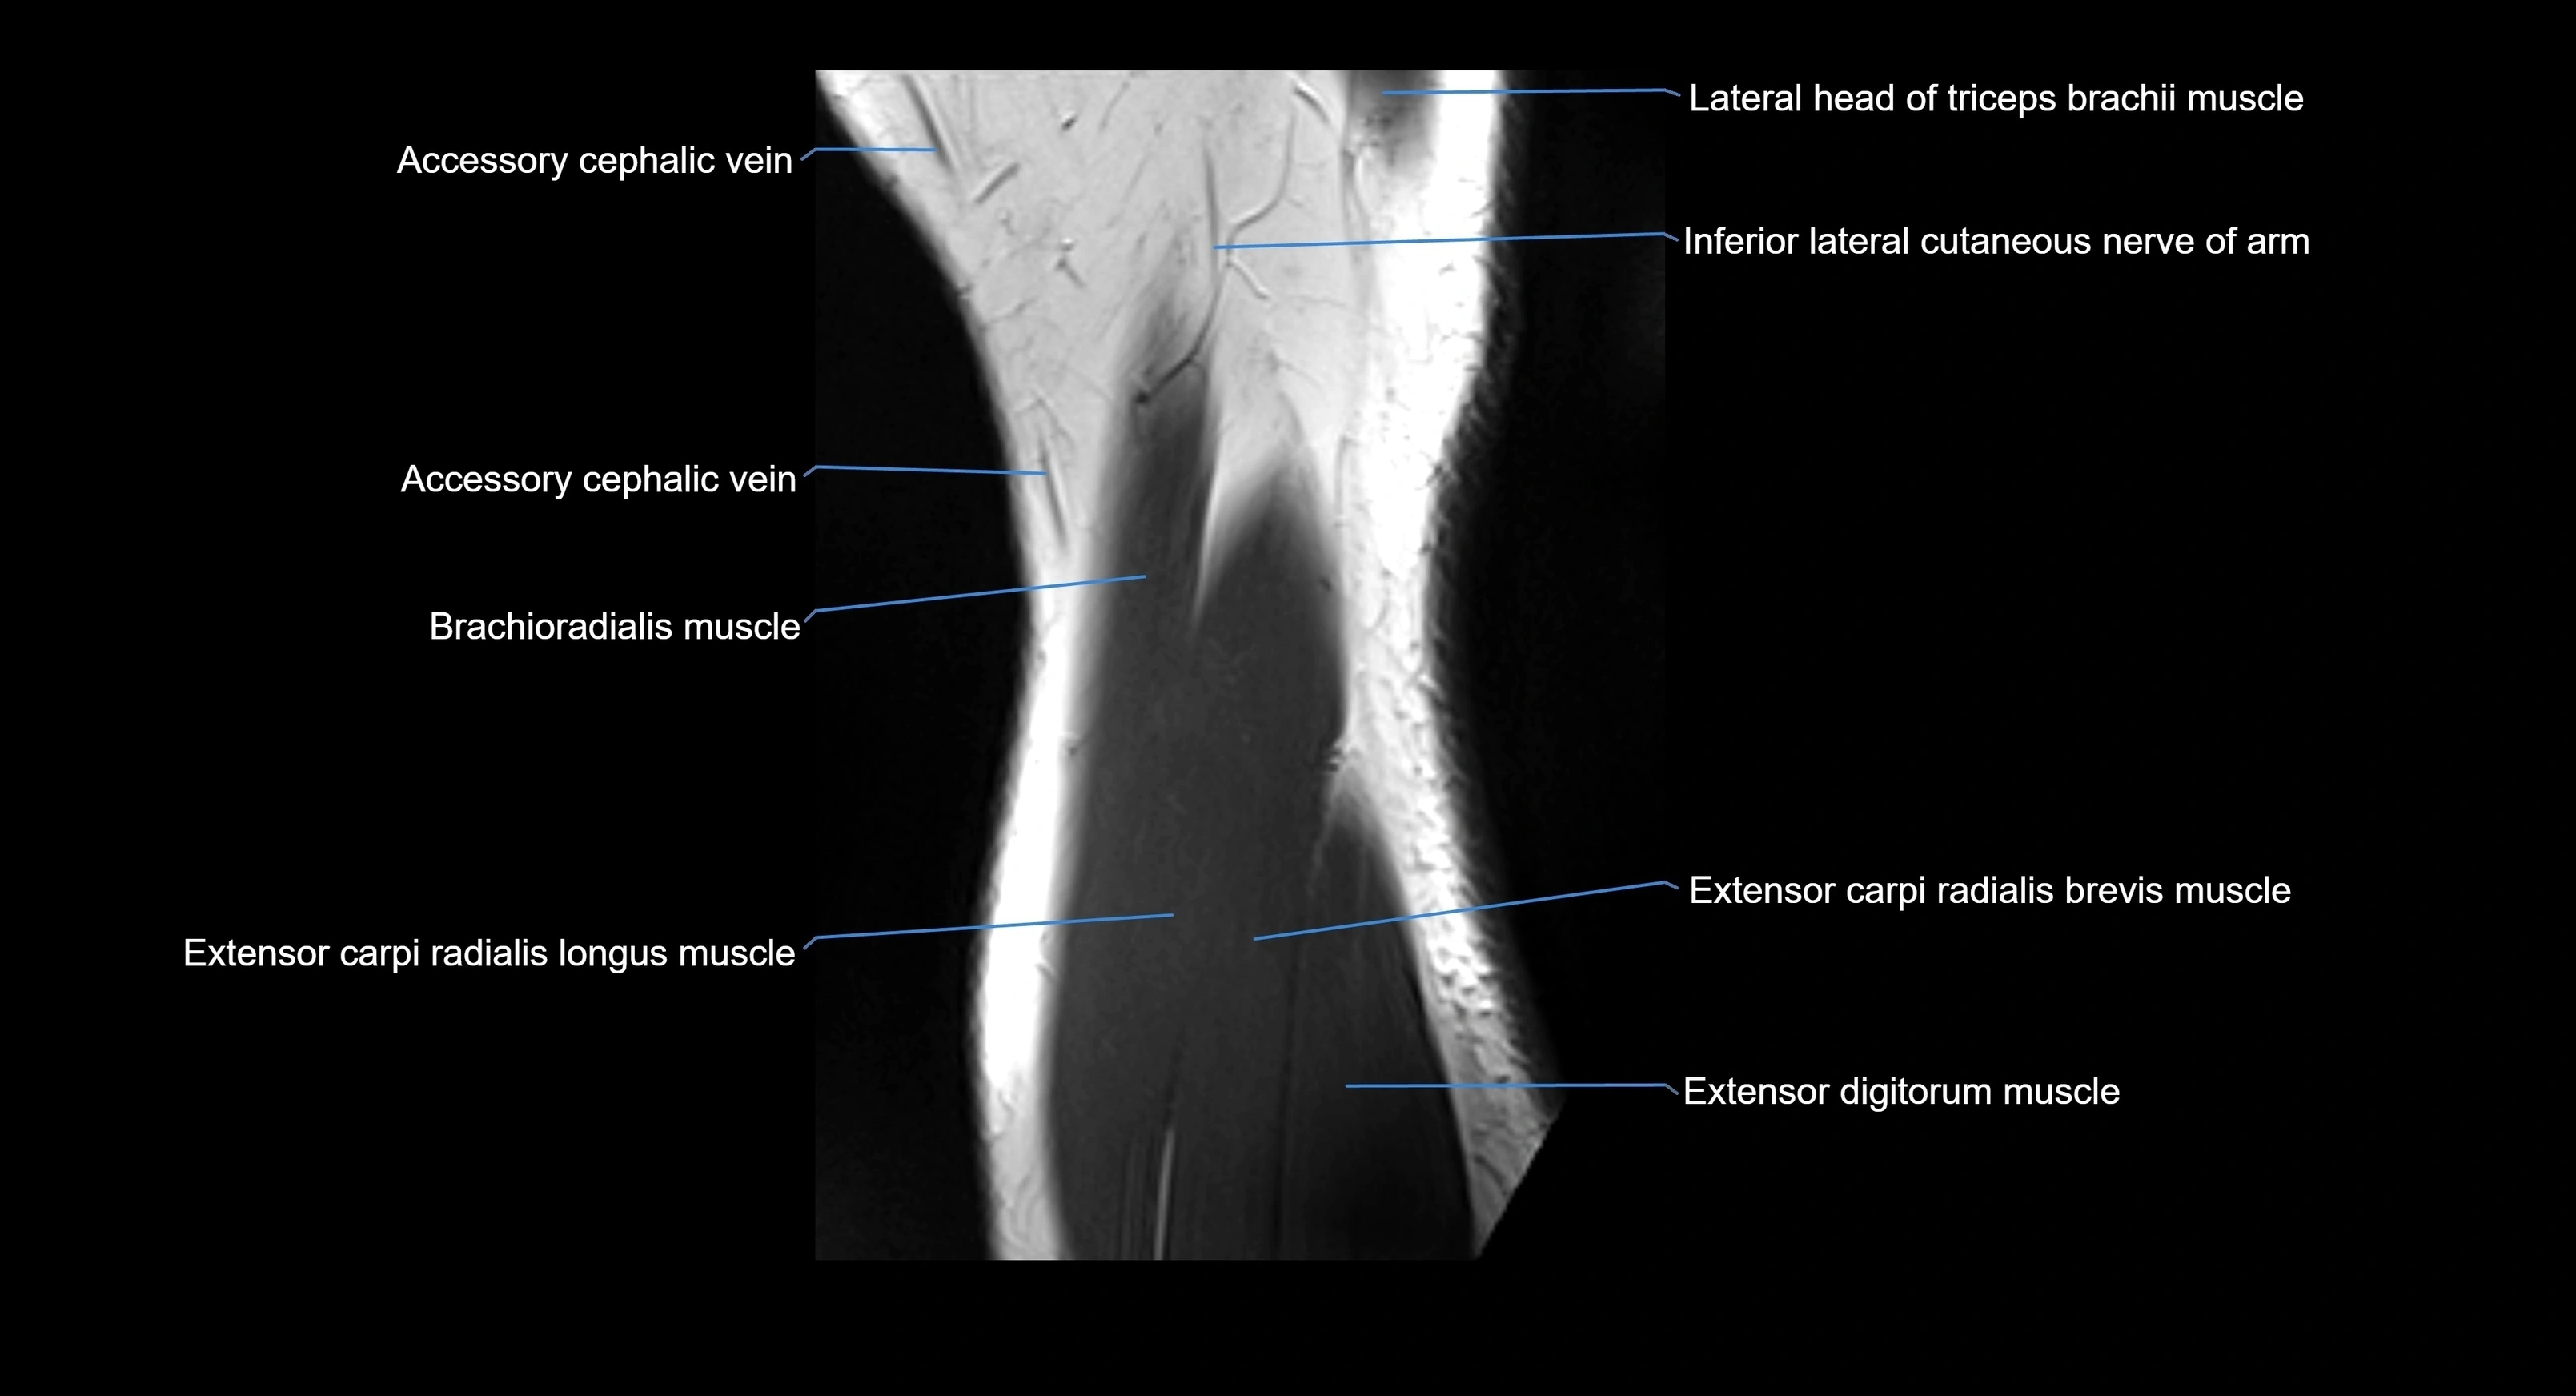

MRI image

image